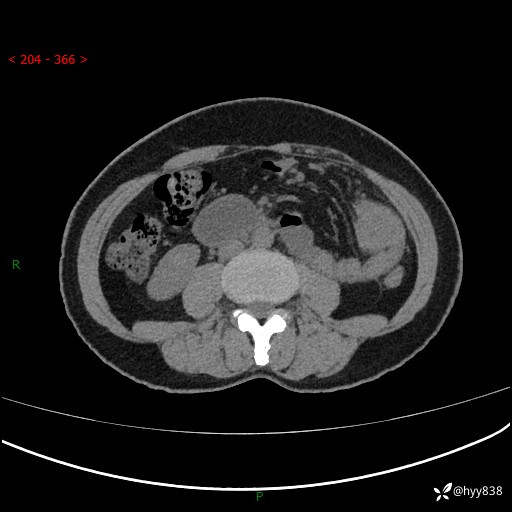

上腹部CT平扫